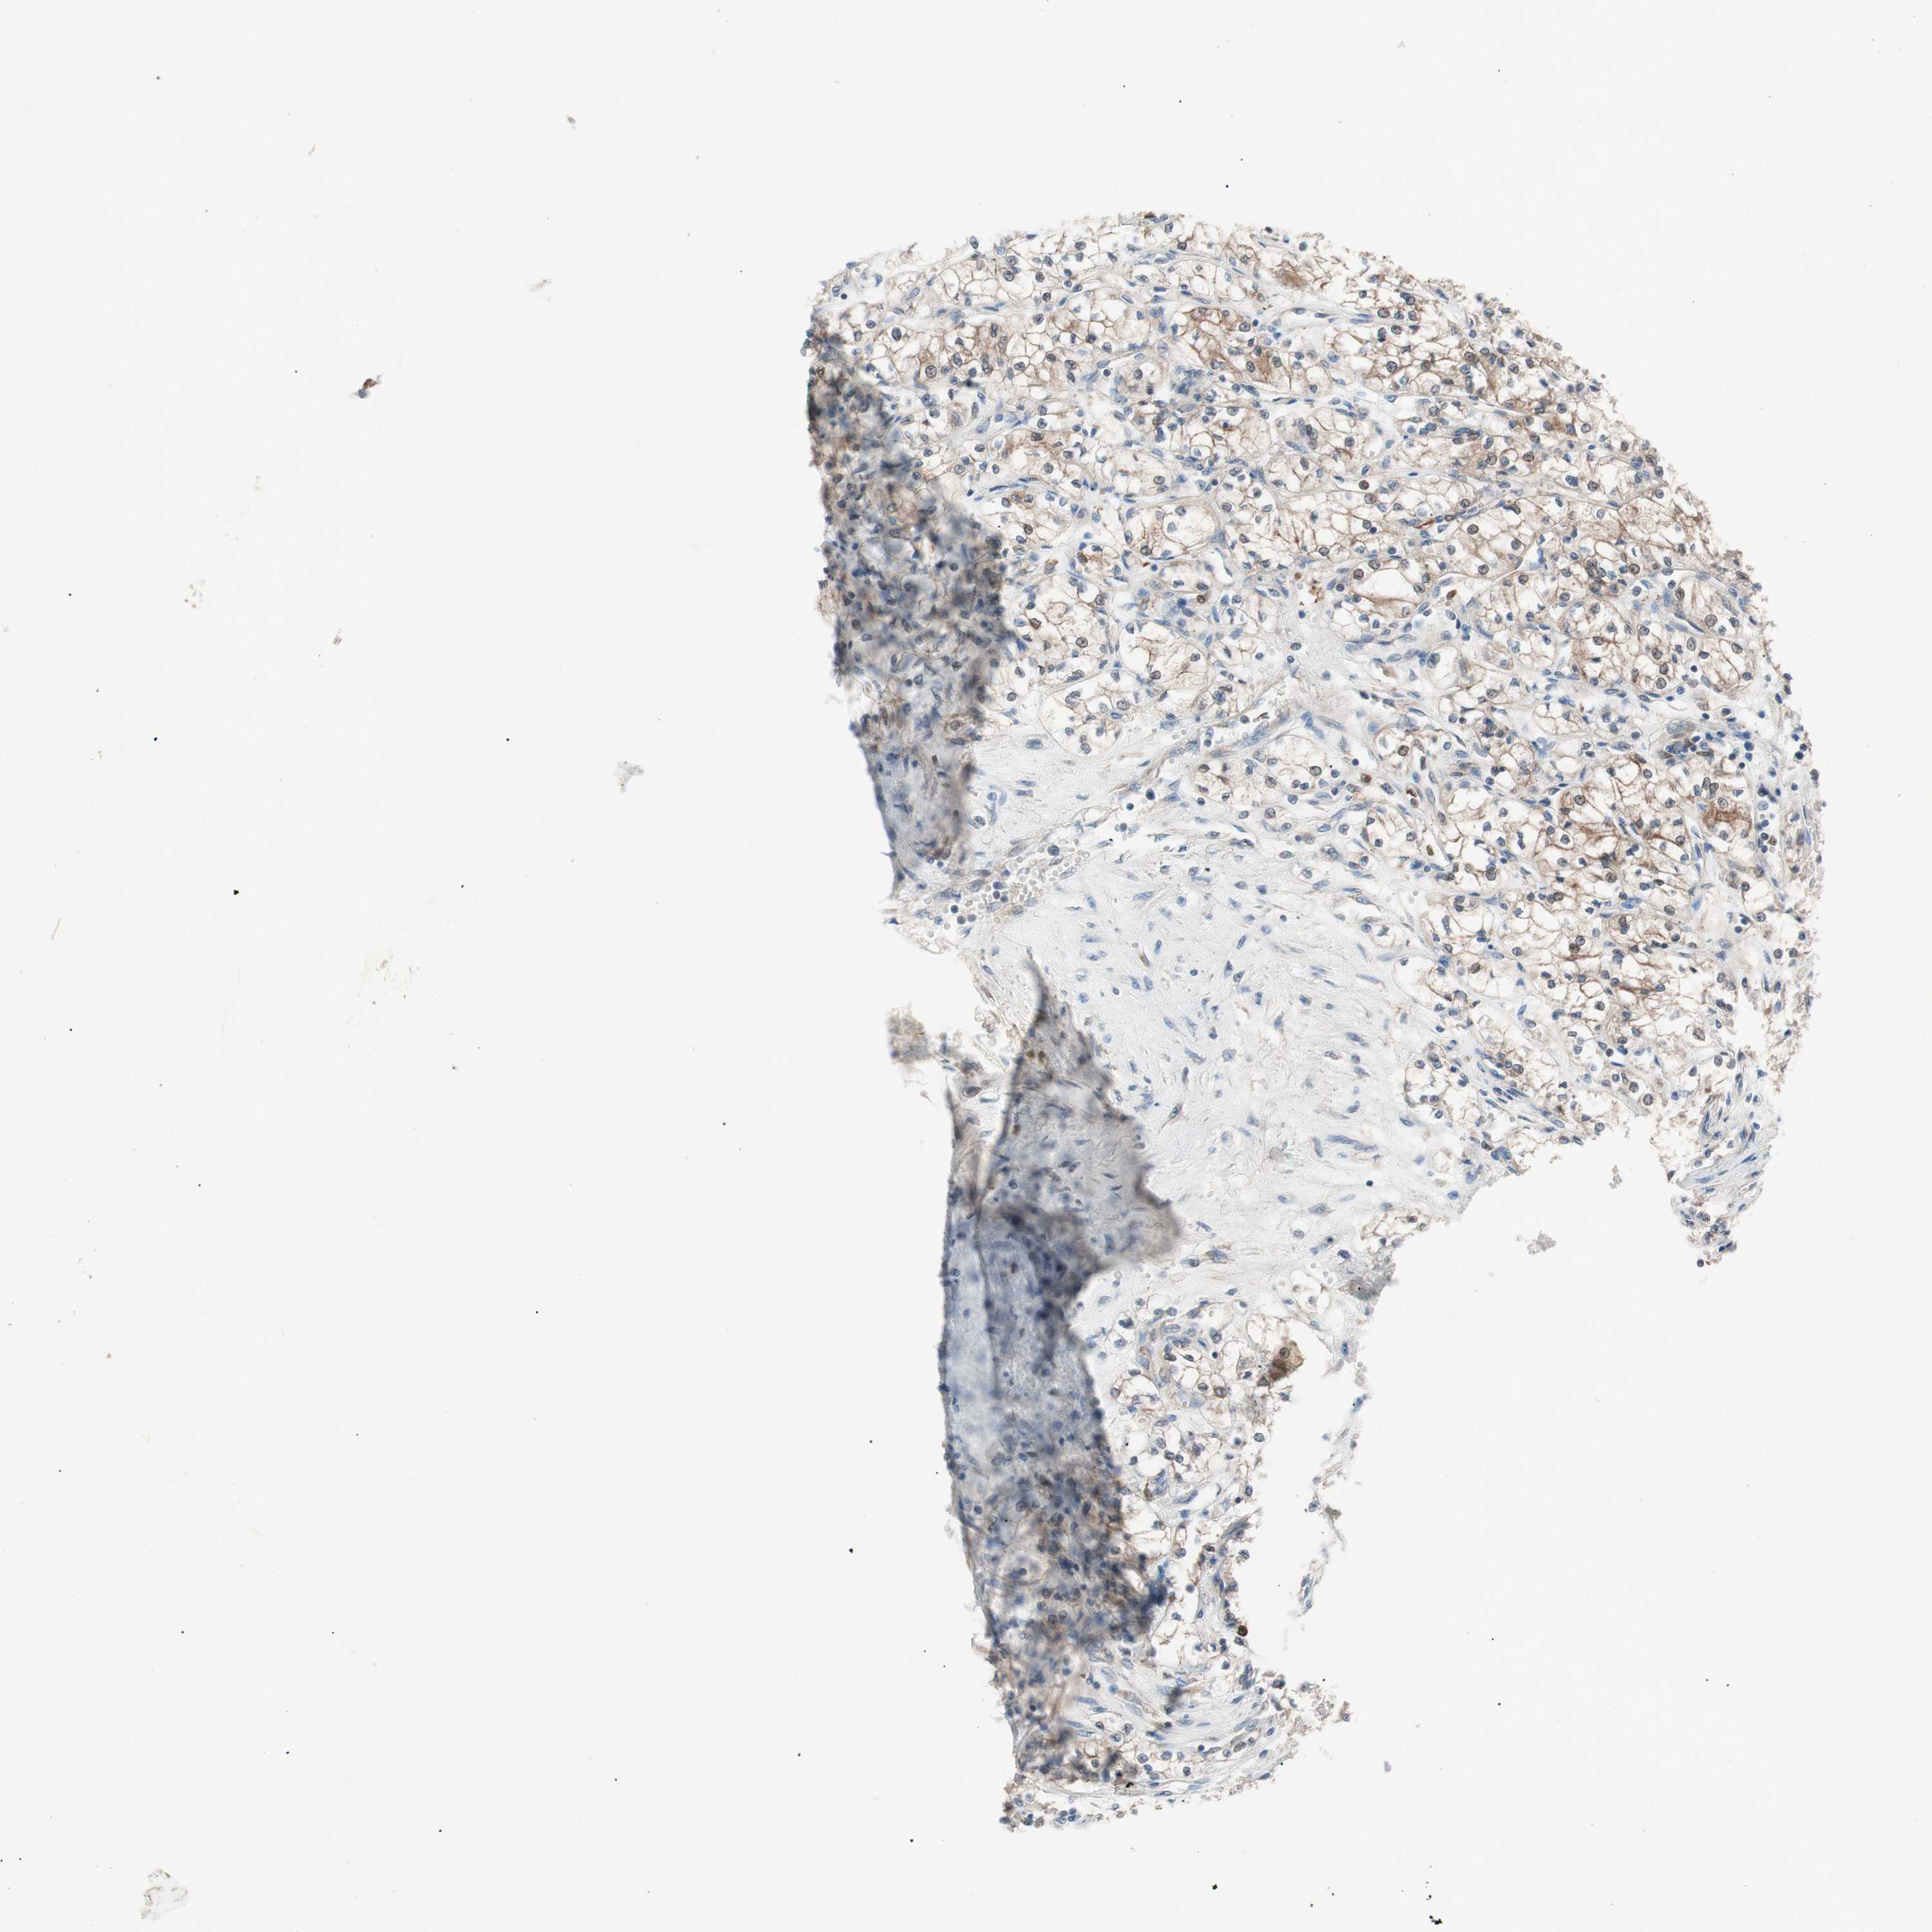

KIDNEY RENAL PAPILLARY CELL CARCINOMA (TCGA) - Interactive survival scatter ploti

The Survival Scatter plot shows the clinical status (i.e. dead or alive) for all individuals in the patient cohort, based on the same data that underlies the corresponding Kaplan-Meier plots. Patients that are alive at last time for follow-up are shown in blue and patients who have died during the study are shown in red.

The x-axis shows the expression levels (FPKM) of the investigated gene in the tumor tissue at the time of diagnosis. The y-axis shows the follow-up time after diagnosis (years). Both axes are complimented with kernel density curves demonstrating the data density over the axes. The top density plot shows the expression levels (FPKM) distribution among dead (red) and alive patients (blue). The right density plot shows the data density of the survived years of dead patients with high and low expression levels respectively, stratified using the cutoff indicated by the vertical dashed line through the Survival Scatter plot. This cutoff is automatically defined based on the FPKM cutoff that minimizes the p-score. The cutoff can be changed by dragging the vertical line or by entering a cutoff value in the square labeled "Current cut-off".

Under the Survival Scatter plot the p-score landscape (black curve; left axis) is shown together with dead median separation (red curve; right axis). Dead median separation is the difference in median mRNA expression between patients who have died with high and low expression, respectively. It is calculated as follows: median FPKM expression of dead patients with high expression - median FPKM expression of dead patients with low expression. This is intended to aid the user in visually exploring custom cutoffs and the associated p-scores and dead median separation.

Individual patient data is displayed and can be filtered by clicking on one or more of the category buttons on the top of the page. Categories describing expression level and patient information include: high, low, alive, dead, female, male and tumor stages. The scale of the x-axis can be toggled between linear and log-scale by clicking on the "x log" button. Mouse-over function shows TCGA ID, patient information and mRNA expression (FPKM) for each patient.

& Survival analysisi

Kaplan-Meier plots summarize results from analysis of correlation between mRNA expression level and patient survival. Patients were divided based on level of expression into one of the two groups "low" (under cut off) or "high" (over cut off). X-axis shows time for survival (years) and y-axis shows the probability of survival, where 1.0 corresponds to 100 percent.

FAAH is potential prognostic, high expression is favorable in Kidney Renal Papillary Cell Carcinoma (TCGA)

Best expression cut offi